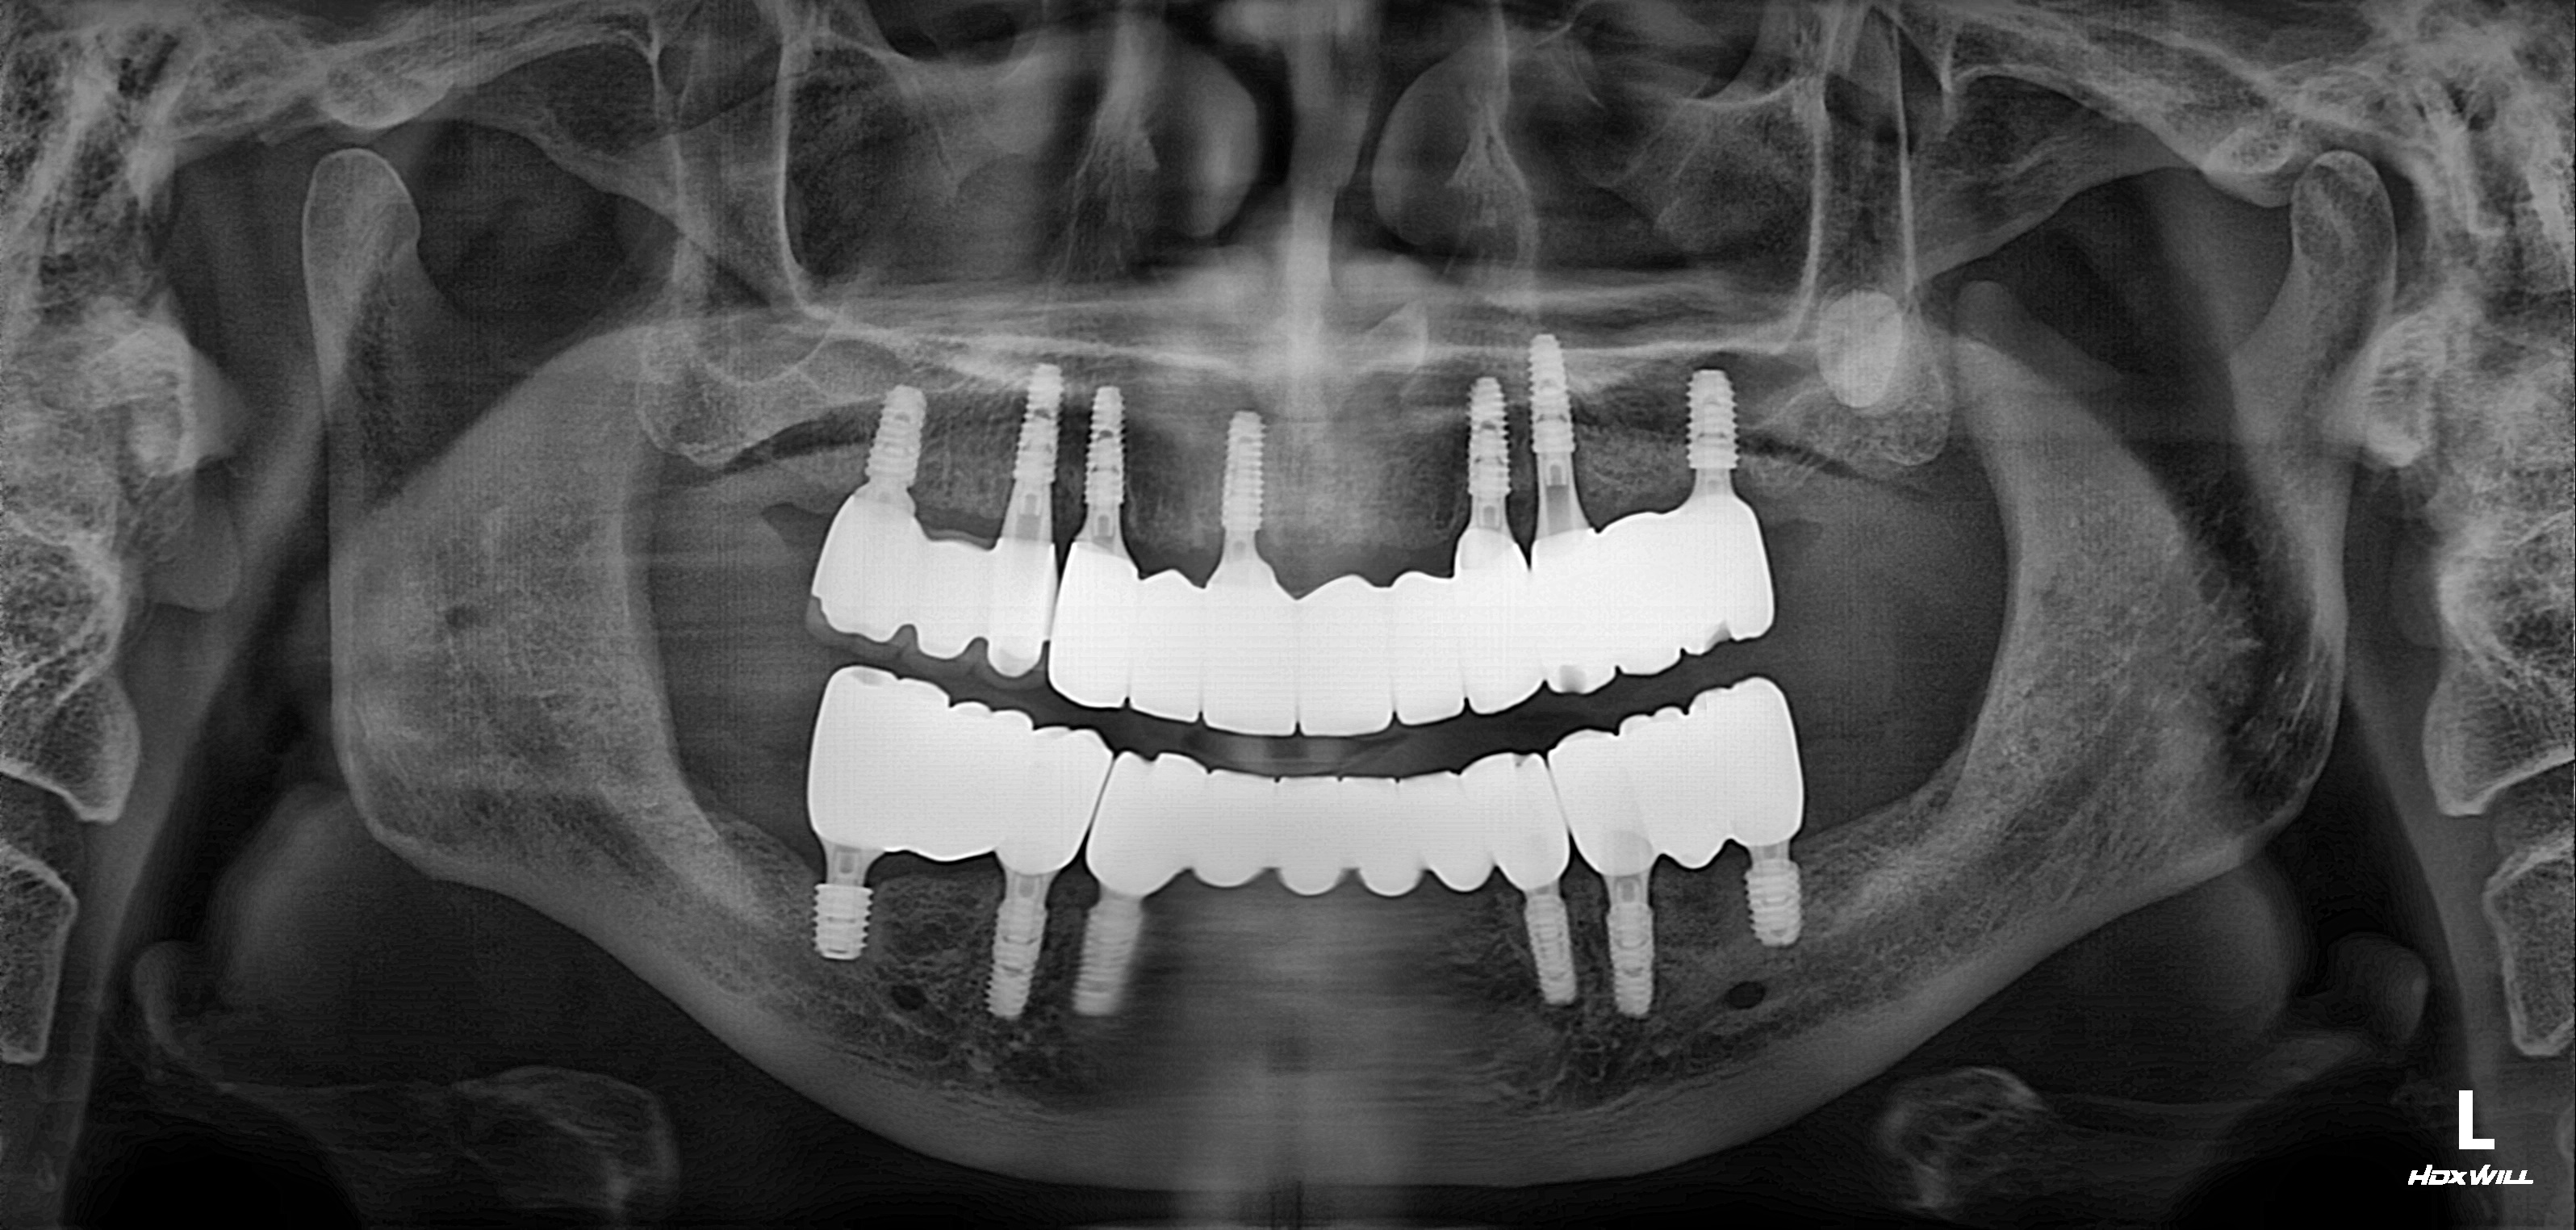

전악임플란트 식립사례

전후사진